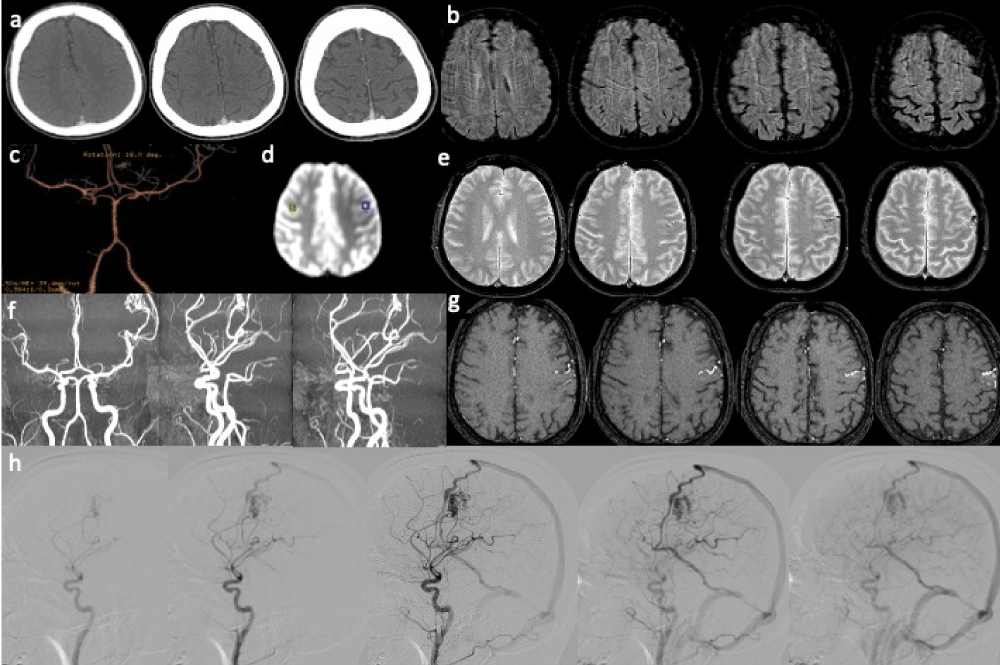

Figure 4: Arteriovenous malformation. Acute focal neurologic symptoms. Stroke code: 45 years old male presenting with right hemiparesis, weakness, impairment of speech and alteration of consciousness (NIHSS 6). a) No-contrast brain CT and b) CTA findings were negative. d) T2- weighted MRI shows ectasic surface vessels in the left frontal lobe, better appreciated on (e) SWI. f) Quantitative ASL (OLEA sphere 3.0): focal hypoperfusion corresponding to the left Rolandic cortical area adjacent to ectasic cortical vessels. 3D-TOF MRA(g,h) (single slice and MIP) shows the abnormal dilated vessels embedded left frontal lobe and (f) the DSA on lateral left carotid angiograms demonstrate the left frontal AVM with a nidus supplied by an enlarged branch of MCA. Note the early drainage to a frontal cortical vein into the superior sagittal sinus (and via an internal cerebral vein to the straight sinus). Diagnosis: frontal AVM inducing focal hypoperfusion of left Rolandic cortical area caused the acute neurologic symptoms.